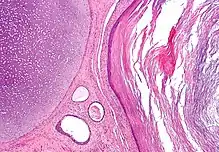

- Ectodermo: Es la capa germinal más externa. Es el origen de la piel y el tejido nervioso, el tubo digestivo superior (estomodeo), la epidermis y sus anexos (pelo y uñas) y las glándulas mamarias.

- Mesodermo: Es la capa germinal media. Se origina a partir de la masa celular interna y se sitúa entre el endodermo y el ectodermo. Es el origen del sistema esquelético, los músculos, el sistema circulatorio y el aparato reproductor.

- Endodermo: Es la capa germinal más interna. Aparece siempre cuando una capa de células se proyecta hacia afuera a partir de la masa celular interna que crece alrededor del blastocele. Es el origen del intestino, el hígado, el páncreas, los pulmones, los riñones, y la mayor parte de órganos internos.